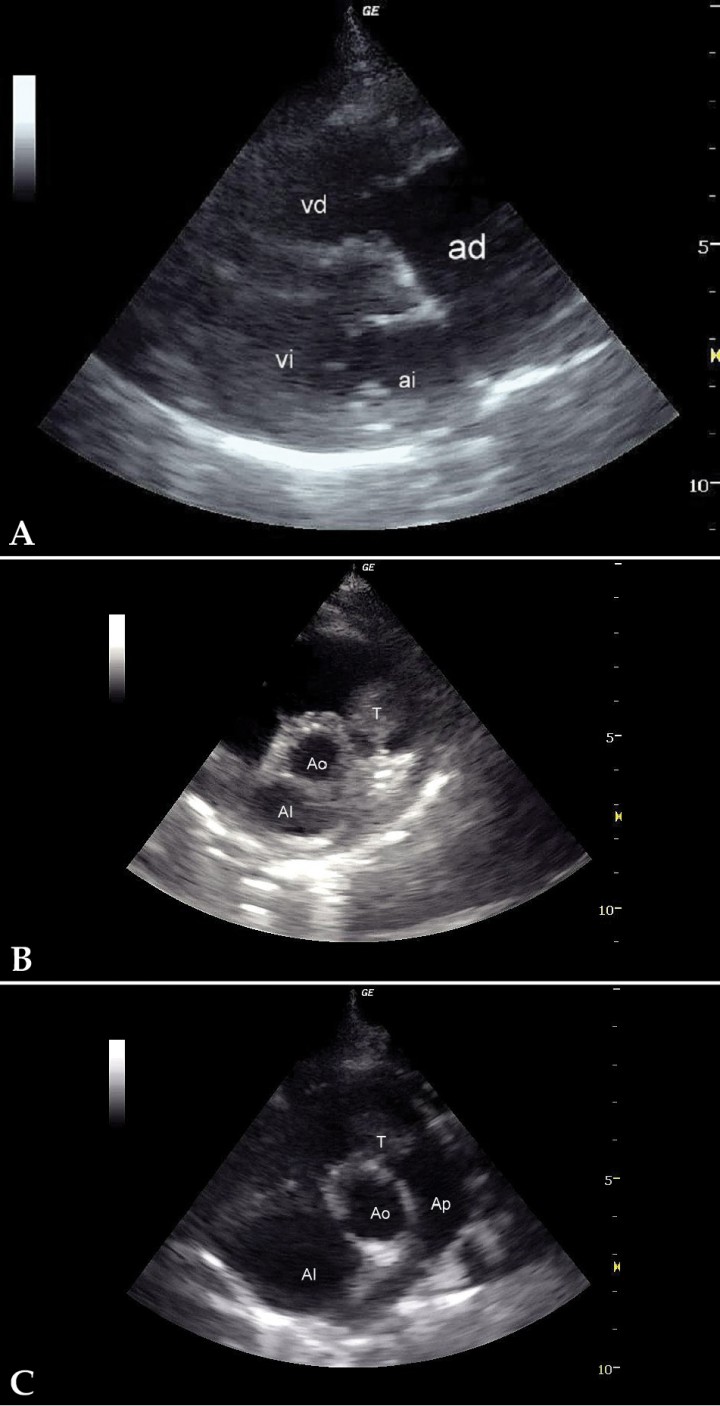

- Dilatación de moderada a severa de cámaras derechas, especialmente atrio derecho (Fig. 3A), con hipertrofia excéntrica del ventrículo derecho.

(A) Corte paraesternal derecho, eje largo, 4 cámaras. Severa dilatación del atrio derecho. (B) Corte paraesternal derecho, eje corto. Presencia de una masa intraluminal en tracto de salida derecho. (C) Corte craneal izquierdo. Presencia de una masa intraluminal en tracto de salida derecho. AD: atrio derecho; AI: atrio izquierdo; VD: ventrículo derecho; VI: ventrículo izquierdo; T: tumor; Ao: aorta; AI: atrio izquierdo; Ap: arteria pulmonar.

- Presencia de una masa intraluminal de dos por tres centímetros en tracto de salida derecho (Figs. 3B y 3C), que produce una obstrucción al flujo de salida y, por tanto, una reducción del caudal a través de la arteria pulmonar. El flujo laminar de salida a 1,4 m/s se vuelve turbulento a su paso por la masa, a la que rodea claramente (Fig. 4), provocando una aceleración del flujo hasta los 2,9 m/s (Fig. 5).

<p>(A) Corte paraesternal derecho, eje corto. (B) Corte craneal izquierdo. Doppler color con flujo sanguíneo rodeando la masa demostrando obstrucción mecánica del flujo. T: tumor; Ao: aorta; Ap: arteria pulmonar.</p>

(A) Corte paraesternal derecho, eje corto. (B) Corte craneal izquierdo. Doppler color con flujo sanguíneo rodeando la masa demostrando obstrucción mecánica del flujo. T: tumor; Ao: aorta; Ap: arteria pulmonar.